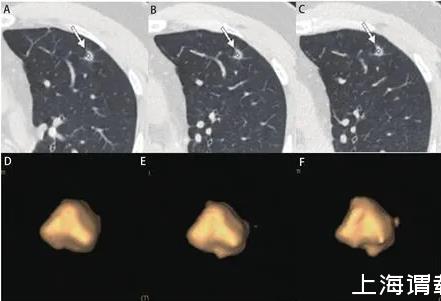

圖6男,56歲,右下葉亞實(shí)性結(jié)節(jié),直徑約為0.9 cm,病理為浸潤性腺癌,腺泡為主。A、B:2013/2/18第一次CT檢查,體積為368 mm3;C、D:2013/5/3檢查,體積為409 mm3;E、F:2014/2/19檢查,體積為485 mm3。初次檢查1年后亞實(shí)性結(jié)節(jié)增大緩慢。